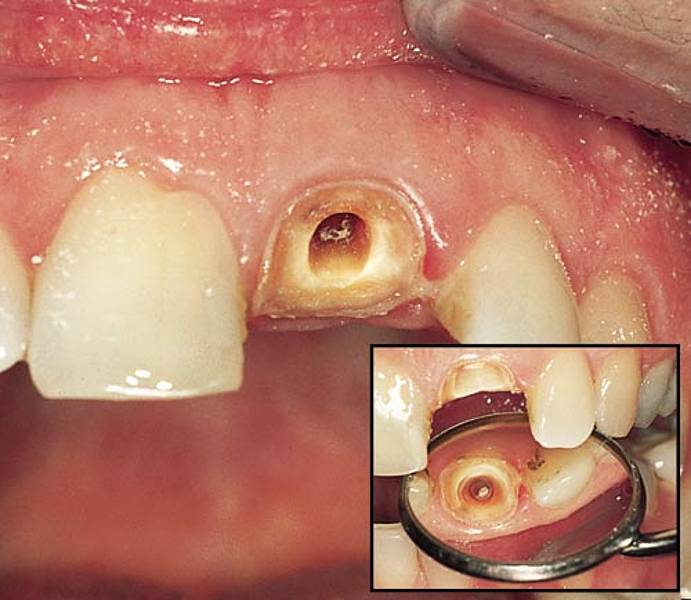

Um Schäden des Zahns zu verhindern und den Zahn zu stabilisieren, ist in vielen Fällen eine Krone empfehlenswert Entweder kann die Krone gelöst und später nach erfolgter Wurzelbehandlung und neu bearbeitet wieder eingesetzt werden.

Ein Zahnbruch kann dazu führen, dass der Zahn letztlich entfernt werden muss, was in den meisten Fällen eine aufwendige und kostenintensive Versorgung mit Zahnersatz wie einem Implantat oder einer Brücke nach. Dies hängt von verschiedenen Faktoren ab, wie dem Zustand der Krone und des darunterliegenden Zahnes nach der Wurzelbehandlung. Auch ein bereits wurzelkanalbehandelter Zahn mit Krone kann Schmerzen bereiten, wobei die Ursache meist eine Entzündung im Bereich der Wurzelspitzen ist.

wieso nach einer wurzelbehandlung stift + krone Wurzelbehandlung, Zahnimplantat, Behandlung. Renne schon seit 2 Jahren mit einem wurzelbehandelten Zahn umher, weil der bis jetzt immer wieder Zicken gemacht hat, da wäre eine Krone nicht sehr angebracht gewesen, weil man danach nur noch hätte ziehen können. Eine Krone kann in diesem Fall dazu beitragen, das Erscheinungsbild zu verbessern